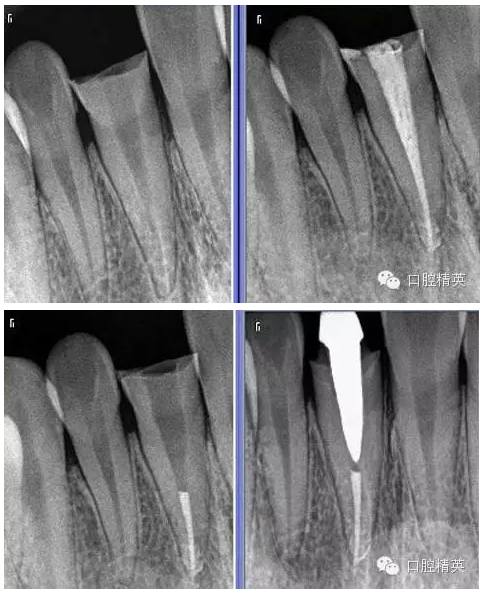

6:術(shù)前后的X-RAY。